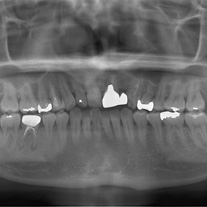

基本的なレントゲンによる撮影をはじめ、根本的な治療をするための様々なテストや検査を⾏います。

⾒た⽬にはわからない初期の⻭周病も、様々な検査⽅法で多⾓的に確認していきます。

⻭周病は⻭を⽀え⾻を溶かす病気です。レントゲンを⽤いて、⻭を⽀える⾻がどのくらい⻭周病により溶かされているかを確認し、重点的に治療が必要な場所などを特定します。